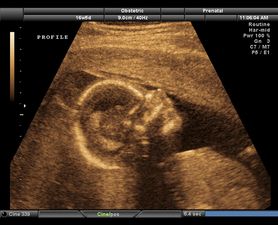

Ultrasound scan images reveal harmful effects of smoking during pregnancy

By Sive O'Brien